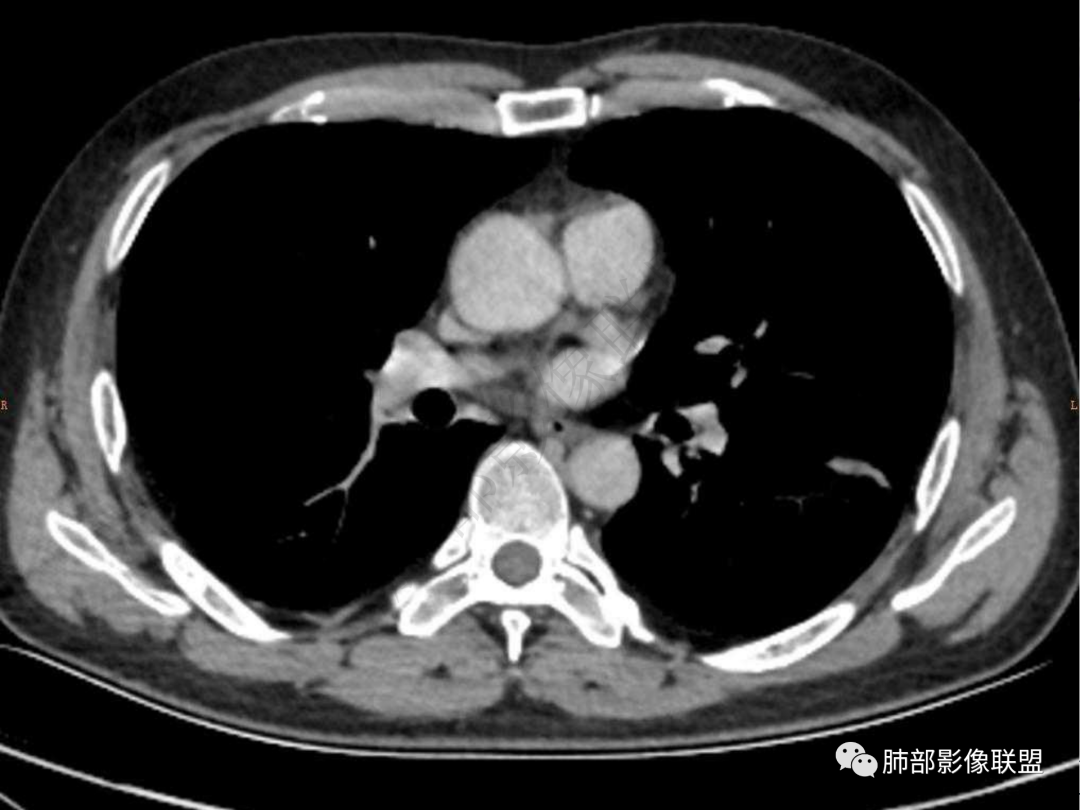

1.中年男性,咳嗽咳痰20余天,间断咯血2周

2.左肺下叶团片影,跨背段及内前基底段,实性部分类椭圆形,密度不甚均匀,可见毛刺及棘状突起,未见典型分叶及胸膜凹陷。病灶上下缘可见相应肺段支气管旁进侧出,管壁轻度增厚,未见狭窄阻塞。

3.周边较大范围磨玻璃影,边界相当模糊,小叶增厚明显。注意叶裂另一侧、左肺舌段亦可见磨玻璃影及增厚的小叶间隔。未见明确卫星病灶。

4.实性部分不均匀环形强化并显示一小范围低密度坏死区或空洞。较之肺窗,整体纵隔窗范围较小,提示病灶并不十分密实。抑或为不同时段图像。

5.双肺门及纵隔未见增大淋巴结。未见胸腔积液。